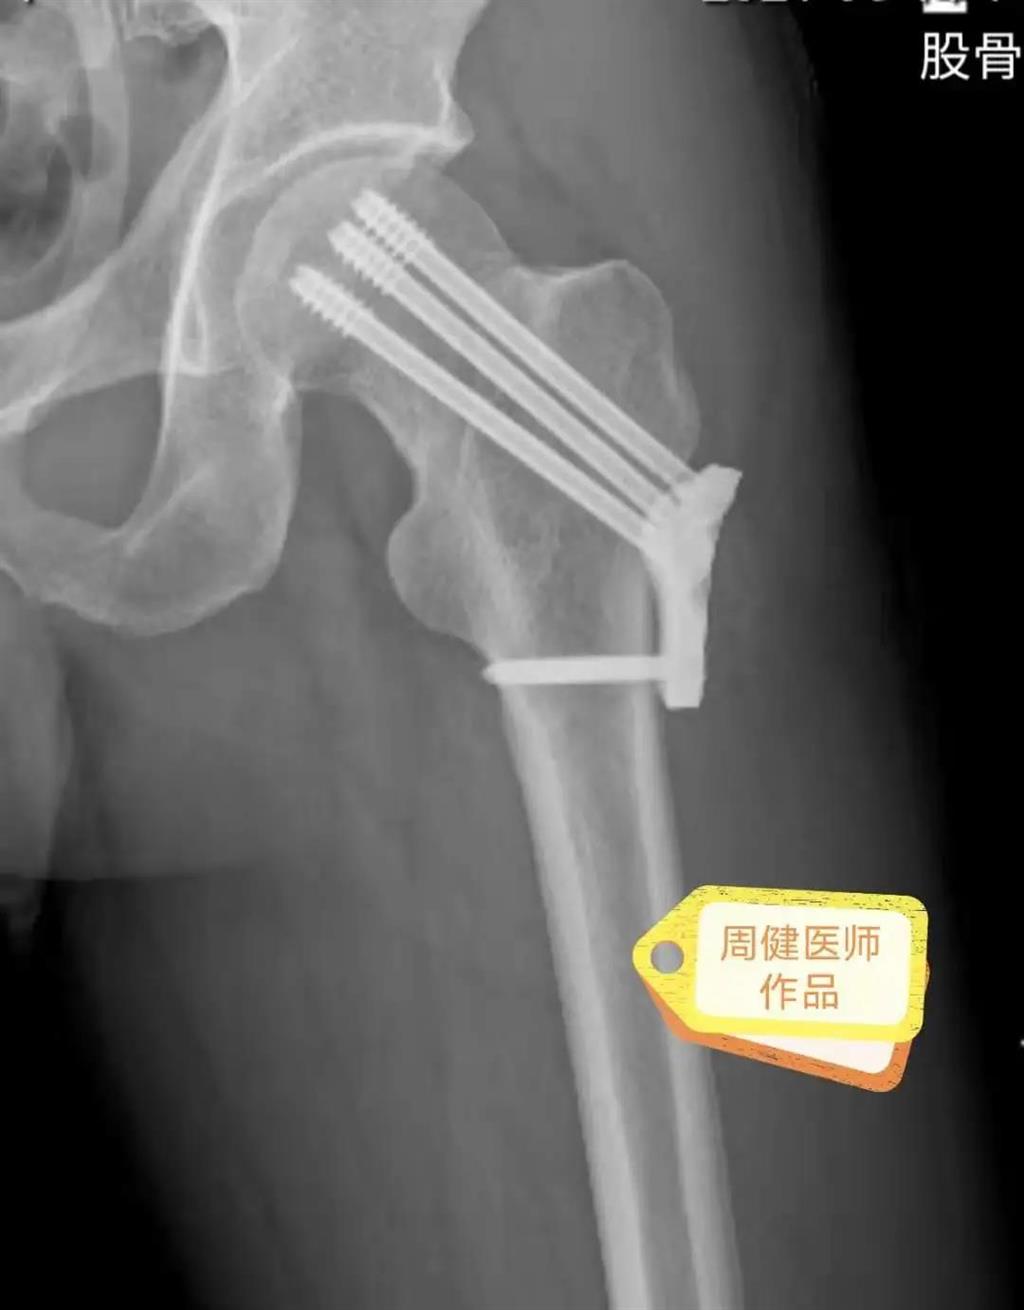

6月30日的“關(guān)節(jié)置換術(shù)”,患者是一位上了年紀(jì)的老人,苦于病痛折磨多年的他四處“求醫(yī)問(wèn)藥”,最后在多位專家醫(yī)師及病友地力薦下選擇了和平國(guó)際醫(yī)院,在醫(yī)師團(tuán)隊(duì)“偷天換日”般的手術(shù)后,老人成功告別了苦纏多年的病痛。

周健說(shuō),這場(chǎng)“關(guān)節(jié)置換術(shù)”對(duì)于他們團(tuán)隊(duì)而言其實(shí)算是比較普通的手術(shù),因?yàn)樽鲞^(guò)很多同類的手術(shù),成功案例繁多,因此在手術(shù)操作上有較多地實(shí)操經(jīng)驗(yàn)。“不過(guò)話雖如此,作為醫(yī)生我們對(duì)于每一場(chǎng)手術(shù)都會(huì)全力以赴,這是為醫(yī)者的職責(zé)也是義務(wù)。”